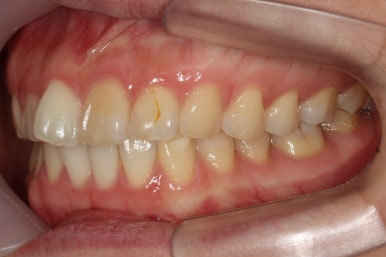

부산앞니교정 키다리아저씨치과에 처음 내원하셔쓸 당시의 입안 모습입니다.

앞니가 살짝 삐뚤어진 것을 볼 수 있고, 삐뚤어진 사이에서 약간의 틈새도 있었습니다.

예전에 치료 받으셨던 앞니 부분에 약간의 변색도 와서 미적으로 좋지 못한 상황이였습니다.